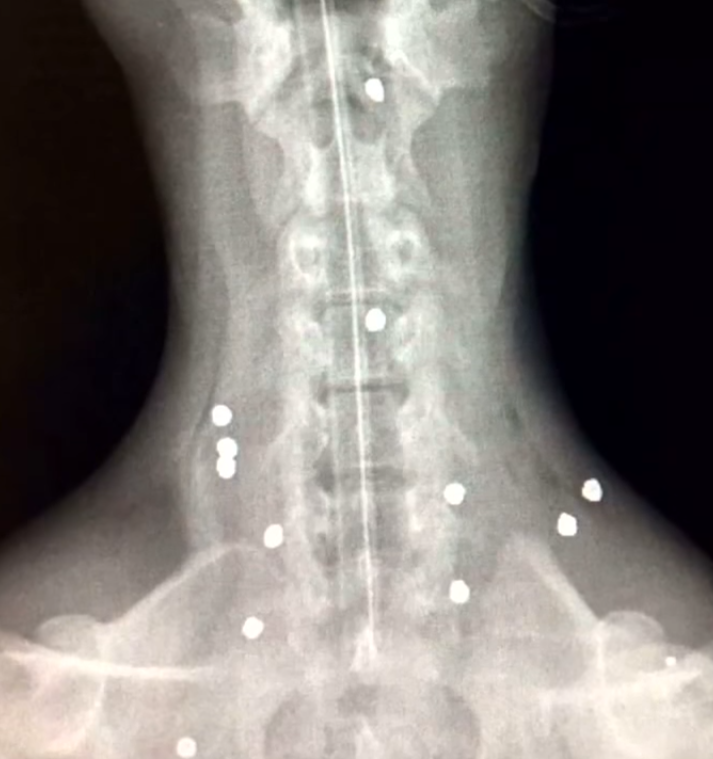

When they looked at her X-Ray results, they were shocked at what they saw. This paralyzed baby jaguar was shot 18 times! She was such in bad shape that doctors were not positive if she would make it.

D’Yaria underwent two spinal surgeries, and the surgeons couldn’t believe that she survived the operations. Not long after the surgical procedure, she was already struggling to stand and walk around.